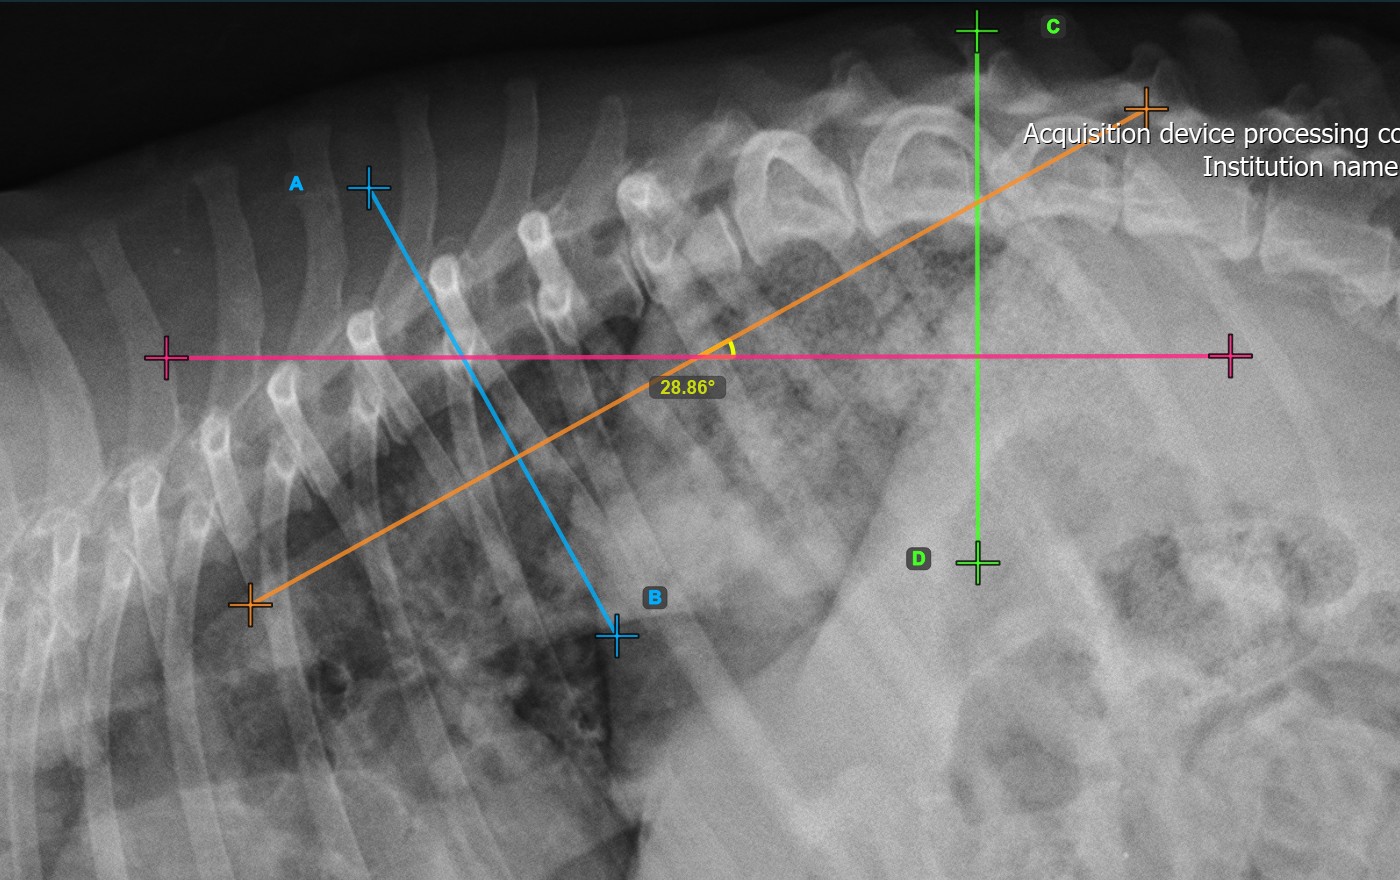

Mark the second vertebral line on the spine to calculate the deformity.

Identify the vertebral endplate at the opposite end of the largest spinal curve deformity. Place the start and end point of the second vertebral line precisely along the identified endplate. Adjust each point on the scene to better align the line with the endplate if needed.

The Cobb Angle measurement will be automatically calculated and completed once the two vertebral lines are placed, indicating the angle of spinal curviture in degrees.

The image below represents a typical placement of the second vertebral line.

Modify the position and orientation of the two vertebral lines to automatically recalculate the Cobb Angle.